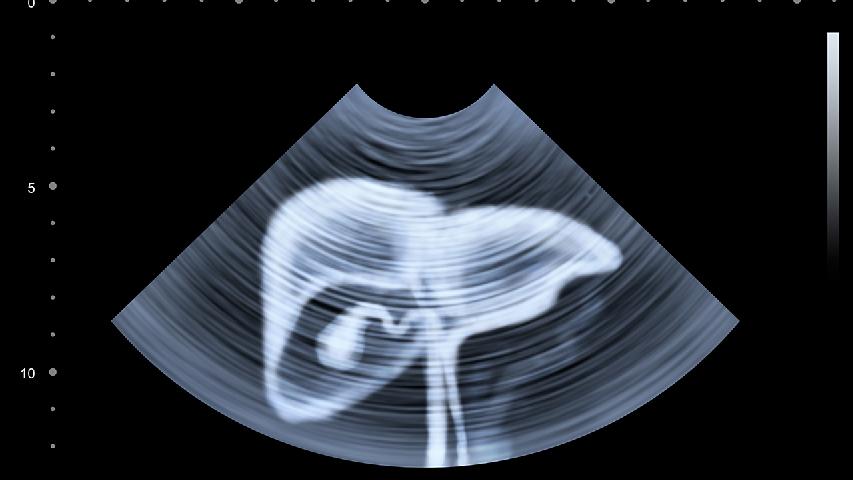

肝癌早期可能无明显表现,进展期常见症状包括右上腹隐痛、食欲减退、消瘦乏力,终末期可能出现黄疸、腹水。肝癌形成主要...